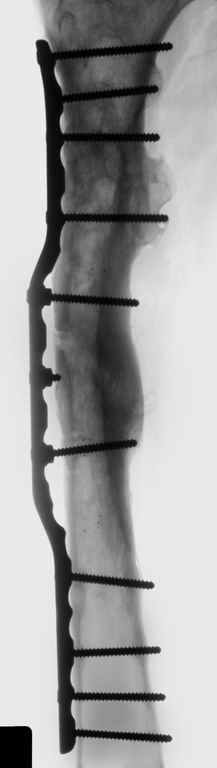

Leonid Pollyak 27 Ноябрь 2004, 11:17

Уважаемые коллеги! Большое спасибо за живой отклик и предложения по тактике лечения. Больной произведен первый этап - стержневой аппарат издвух баз, кортикотомия, остеоклазия и начата коррекция в аппарате. Почти исправлен угол, не сегодня укорочение 2см. Когда завершим коррекция, представлю рентгенограммы.

Leonid Pollyak 02 Январь 2005, 22:42

В ноябре этого года я обращался с просьбой о помощи в выборе тактики лечения больной с деформацией бедра на почве фиброзной дисплазии. Были получены интересные и очень полезные советы по операции.

Хотелось бы показать, что получилось в результате.

Операция выполнялась с помощью А.Н.Челнокова. Очень понравилась технология выполнения блокируемого остеосинтеза с использованием спицевого дистрактора, модифицированный гвоздь с латерализованным проксимальным отделом и возможностью многовинтовой фиксации проксимального и дистального участков бедра.